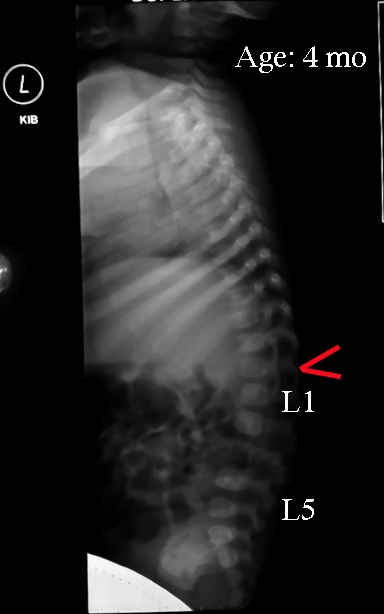

Check out the image of a newborn’s spine. This shows the difference between an adult spinal curve and newborn’s spinal curve. In the photo the peak of the spine is marked in red. The area marked “L1” is where the nerves for the intestines comes from. Those nerves pass through the dark spaces at the back of the square vertebra. In adults, the peak of the kyphosis (the primary curve, think of what “fetal position” looks like) is between the shoulders. In infants who haven’t started pushing up to crawl, bringing the pelvis up into flexion (as is done during a traditional diaper change) straightens the lumbar curve, then the spine bends at this axis. As the lumbar curve becomes more established with crawling, this kyphotic peak moves up the spine into the area of the true rib cage and no longer causes posterior migration of moveable segments during pelvic flexion. You can see now why a subluxation in this area might cause such a problem.